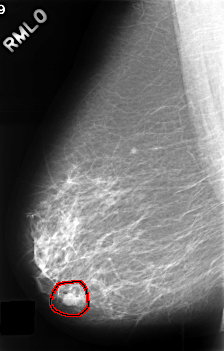

FILE: C_0390_1.RIGHT_MLO.OVERLAY

TOTAL_ABNORMALITIES 1

ABNORMALITY 1

LESION_TYPE MASS SHAPE LOBULATED MARGINS CIRCUMSCRIBED

ASSESSMENT 4

SUBTLETY 5

PATHOLOGY BENIGN

TOTAL_OUTLINES 1

BOUNDARY